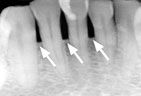

Periodontitis Periodontitis